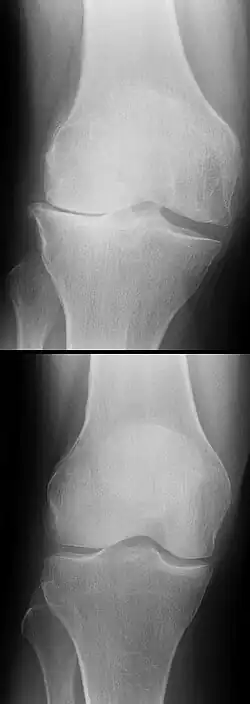

Les radios n'apportent aucune contribution immédiate au diagnostic de rupture de LC. Les deux LC sont invisibles à la radio, déchirés ou non. La seule utilité de la radio ne peut servir qu'au diagnostic des complications osseuses possibles.